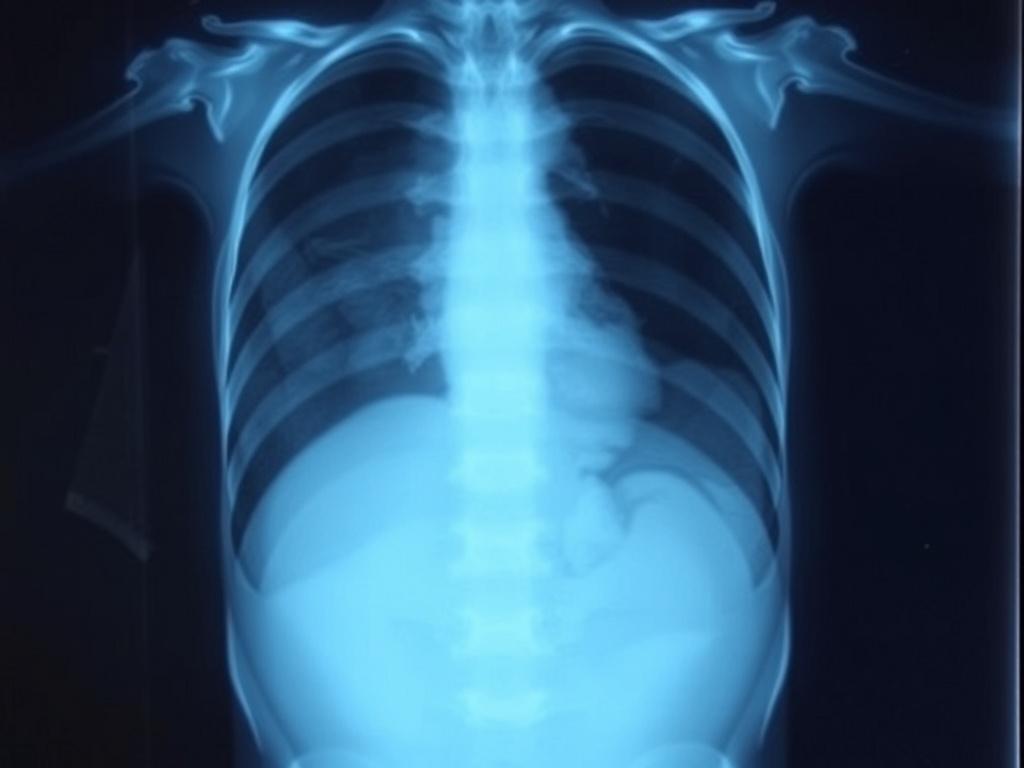

Рентген помогает врачу увидеть, что происходит в животе, когда требуется быстрый ответ. Снимок показывает:

уровень газов и жидкости при кишечной непроходимости

признаки перфорации полого органа по свободному газу под диафрагмой

крупные и средние инородные тела, например монеты, батарейки, детали игрушек

плотные камни, чаще в почках и мочеточниках

выраженный каловый застой при запоре

Также рентген помогает понять, нужен ли срочный хирург, УЗИ, КТ или наблюдение.